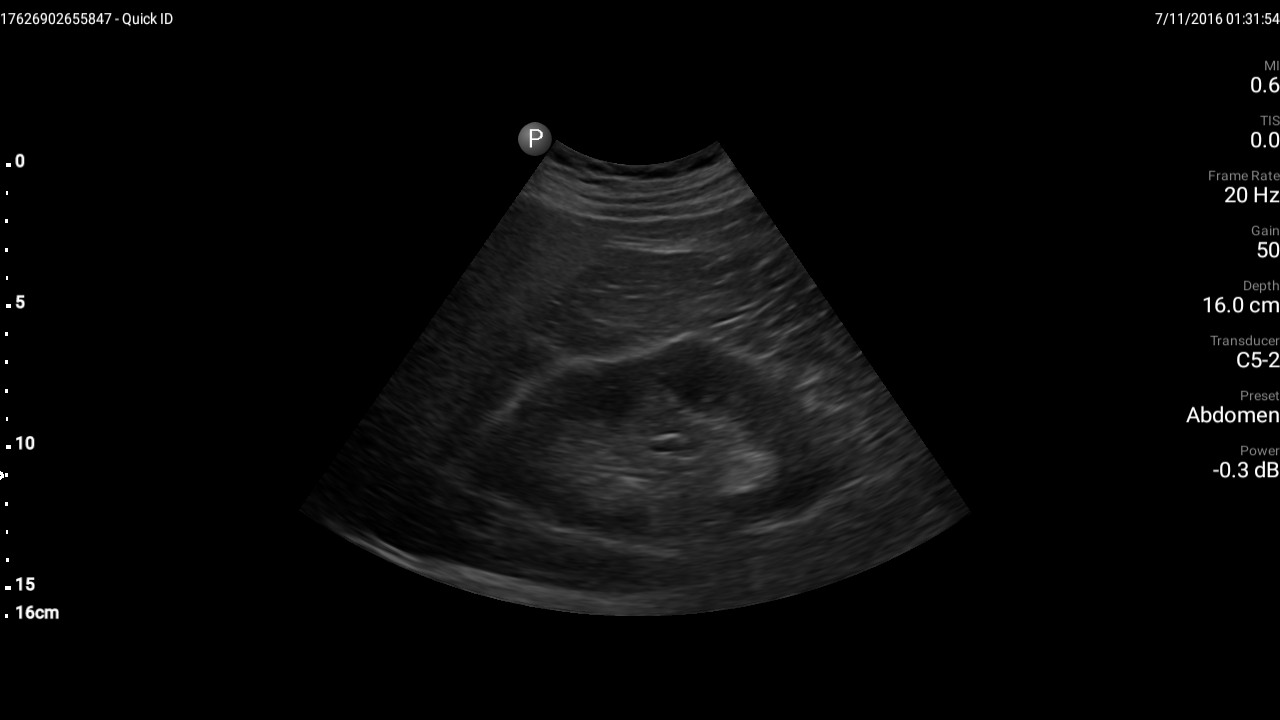

Having complete a 4 week trial using the Philips Lumify, we were suitably impressed with the capability of this highly portable ultrasound machine. Needless to say some of us were sceptical about this machine due to previous poor experience with portable ultrasound equipment (anyone remember the GE VScan?). Summary of Key Points: ?The Philips Lumify is an outstanding portable ultrasound system with great image quality, battery life and ease of use. ?The option of a curvilinear and linear probe means it can be used for most ultrasound applications, we were impressed with its abdominal and vascular imaging capability. ?While the image quality is outstanding and rivals the quality of its larger counterparts (Philips Epiq and iU22), it isn?t designed to be a replacement for a departmental ultrasound machine. The inability to change focal zone, lack of harmonics and the somewhat frustrating probe connection to the tablet were the only slightly frustrating aspects to this device. In the future it would be nice to see compatibility with Apple devices. Additional features to augment its use would be to include some sort of stand in the case for the tablet in order to stabilise it while scanning. ?Overall the Lumify is a capable ultrasound system at an affordable price point and would certainly make a welcome addition to any medical department that uses ultrasound

The Lumify is Philips latest portable ultrasound system which connects to any compatible Android handheld device (tablet or phone). Two transducers are available (Curvilinear and Linear) which plug directly into the device and require no additional power supply. Rather than purchasing the device in its entirety, Philips have launched a monthly subscription model which is currently available in the USA. The android device needs to be provided by the user. The Lumify app is downloadable from the Google Play store.